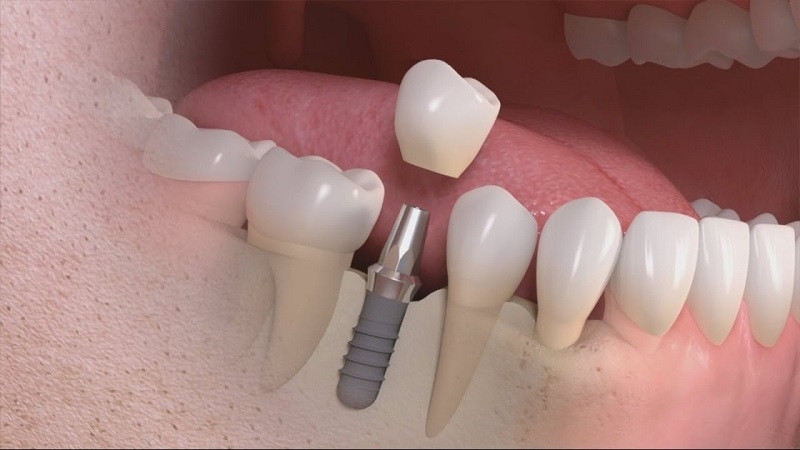

Phương pháp cấy ghép Implant được đánh giá là có hiệu quả cao trong việc điều trị bệnhTuy nhiên, nếu như bạn chọn làm cầu răng sứ và hàm tháo lắp thì chỉ cần phục hình được phần thân răng ở trên nướu mà không có chân răng. Điều này không thể nào ngăn chặn được hiện tượng tiêu xương hàm. Do đó, chỉ có duy nhất một phương pháp là cấy ghép Implant mới có thể thay thế được răng mất mà không làm tiêu xương. Phương pháp này được thực hiện bằng cách cắm trực tiếp vào trong xương hàm, sau đó sẽ thông qua khớp nối Abutment để nâng đỡ cho mão răng sứ phía trên nhằm tạo thành một chiếc răng Implant hoàn chỉnh.

Nhờ có chân răng Implant có tác dụng tạo ra lực kích thích khi ăn nhai vào trong xương hàm, nên cần đảm bảo mật độ và chất lượng xương không bị suy giảm. Điều này cũng giúp ngăn chặn hiện tượng tụt lợi, lệch khớp cắn và mất cân đối khuôn mặt.